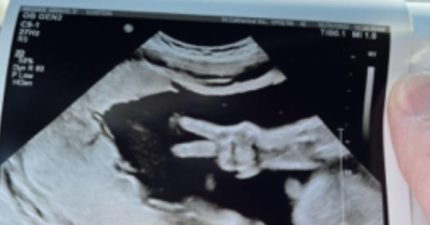

奇蹟瞬間!媽媽照超音波「寶寶肚中比YA」 爸爸傻了:當時突然就有2隻手指頭伸出來

February 6, 2023